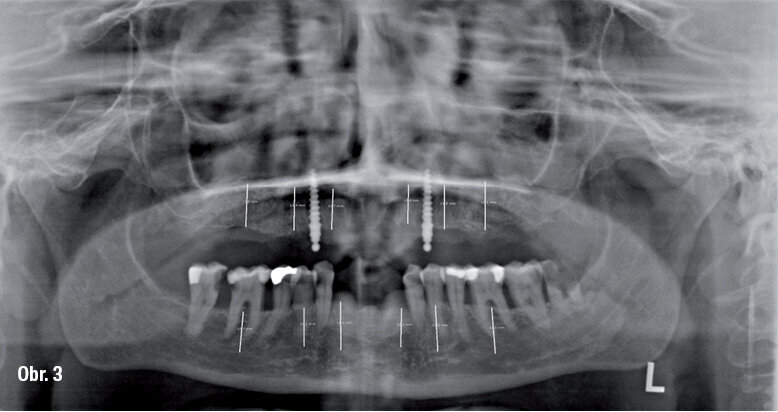

53letá pacientka se dostavila do naší praxe s dotazem, zda v jejím případě existují nějaké možnosti fixní zubní náhrady. Její dosavadní lékařka jí oznámila, že všechny zbývající zuby se musí kvůli špatnému stavu parodontu extrahovat (obr. 1). Zubní lékařka již vyrobila horní a dolní celkovou protézu jako imediátní náhradu. V rámci akutního zubního ošetření musely být při první konzultaci v naší praxi extrahovány čtyři dolní řezáky kvůli silnému stupni viklavosti (obr. 2) a nasazena imediátní náhrada těchto zubů.

Výchozí situace na rentgenovém snímku

OPG snímek po prvním chirurgickém zákroku s plánováním pozic pro implantáty